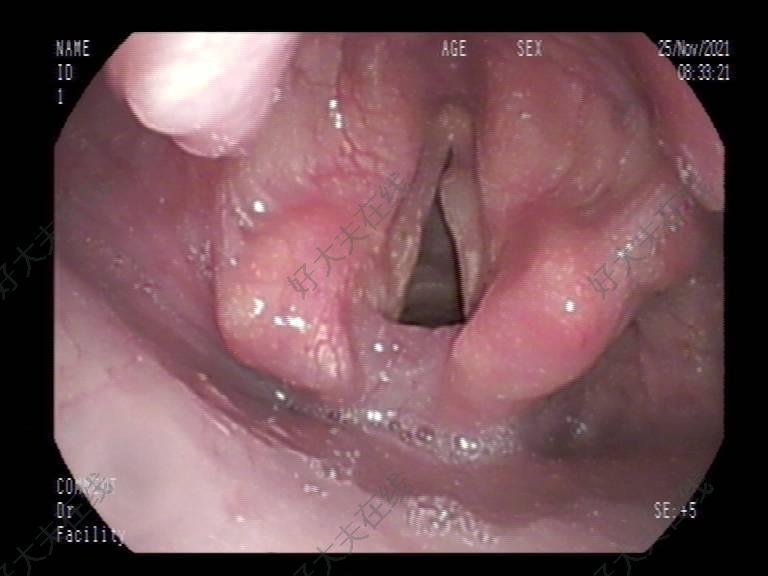

知否,知否(系列六):咽喉部乳头状瘤的科学认知

最近,有许多患者向我咨询,说检查时,发现咽喉部有乳头状瘤,在网上一查,说什么“妖魔鬼怪”的都有,有的感到紧张和不安,有的感觉像天塌下来一样。提出来的问题主要集中在以下几个方面:(1)会不会癌变;(2)怎么得的;(3)会不会传染;(4)如何治疗;(5)会不会复发。 在门诊我们能够经常见到咽喉部乳头状瘤的患者,如何科学的看待发生在咽喉部的乳头状瘤,我检索了有关乳头状瘤的国内外相关文献,结合上面大家常问的问题进行了总结,希望能够帮助到患者朋友们和我们的医生同道。 一、乳头状瘤概述 人们对乳头状瘤感到恐惧,主要是由于这个病变的名称有点“吓人”: (1)乳头状:会不会演变成与甲状腺乳头状癌、乳腺导管内乳头状癌等相似的恶性肿瘤呢?其实是不会的,乳头状瘤与这些肿瘤没有任何联系,也完全不一样; (2)瘤:一般老百姓看到“瘤”字,就以为是“肿瘤”或“癌症”,其实“瘤”有良、恶性之分,一般良性肿瘤,称作“瘤”,恶性肿瘤才称为“癌”,这里的乳头状瘤是一个典型的良性肿瘤。 人们对乳头状瘤感到不安的另一个重要原因是乳头状瘤与人乳头状瘤病毒(human papillomavirus,HPV)之间有着密切的因果关系,即感染了HPV后导致乳头状瘤的出现。 人乳头状瘤病毒(HPV)是个什么“鬼”:HPV属于DNA病毒,HPV感染表皮引起的增生性病变称为“疣”,感染粘膜鳞状上皮引起的增生性病变称为“乳头状瘤”。目前已经确定的HPV类型超过150种,依据不同型别HPV致癌危险性高低分为高危型HPV和低危型HPV,高危型HPV(致癌型)主要包括HPV 16、18、31、33、35、39、45、51、52、56、58、59、68、73和82,低危型HPV(或未证实有危险性的型别)包括HPV6、11、40、42、43、44、54、61、62、70、71、72、81和CP6108。宫颈癌是目前发现的与HPV关系最为密切的疾病,宫颈癌及其癌前病变主要是通过性行为感染高危型HPV(主要是HPV16和18型)所引起的,而低危型HPV主要引起良性病变,如生殖器疣(扁平湿疣和尖锐湿疣)和喉乳头状瘤[1]。 二、咽喉部的乳头状瘤会不会癌变? HPV 感染与发生在咽喉部的恶性肿瘤的发生有一定的相关性,但导致咽喉部恶性肿瘤的主要为高危型HPV(主要是HPV16和18型),而诱发咽喉部良性乳头状瘤的主要为低危型HPV(HPV6和11型),因此癌变率是非常低的(1-2%)。但还是要区分对待乳头状瘤的以下几个类型:(1)发病年龄:幼年型和成人型;(2)病变数量:多发型和单发型;(3)病变位置:口腔、咽部还是喉部。其中发生在喉部的多发型乳头状瘤,也称为复发性呼吸道乳头状瘤病(recurrent respiratory papillomatosis,RPP),尽管形态学上是一种良性疾病,但具有复发性及侵袭性,临床治疗十分棘手。RRP由两种HPV类型(HPV 6和HPV11)引起[3], 其中HPV-11型和年龄<3岁是RPP的主要危险因素,往往病情严重,病变侵袭性强[5]。而发生在咽部的乳头状瘤以单发为主,HPV感染率为6%,明显低于喉部[6]。 三、咽喉部的HPV怎么得的? 儿童和成人的HPV感染方式不同: 1、儿童HPV的感染方式:母婴传播是儿童HPV感染的主要途径之一[7]。 2、成人HPV感染的方式:仍然不明,可能是围生期潜伏感染的HPV激活或经口-生殖器途径接触获得{9}。许多研究发现成人HPV感染率与男性有较多的性伴侣、艾滋病感染者、吸烟显著者和高频率的口交有密切联系。另外有研究显示:喉咽返流、单纯疱疹病毒2型和成人发病的RRP之间可能也存在相关性[10,11]。 四、乳头状瘤会不会传染? 患者常会问到,乳头状瘤会不会引起传染,其实这里的传染是指HPV的传染。其实HPV在正常人体的口腔/口咽部就存在。通常情况下,大多数HPV在感染之后几个月内就会消失,而无需进行任何干预,机体通过自身免疫系统使病毒逐渐清除,尤其是低危型HPV更容易被机体清除。成人HPV通过主要性行为传播,但不一定需要插入式性交,与生殖器皮肤接触被普遍认为是一种传播模式。有少许未被清除的HPV以及新感染的HPV可以在口腔及咽喉部潜伏,在人体免疫力低下以及外来刺激(如吸烟、咽喉反流等)的作用下,可能被激活,导致乳头状瘤的发生。目前口腔和咽喉部的HPV检测还没有在临床上常规开展,不如妇科HPV检测的普遍。 五、咽喉部乳头状瘤如何治疗? 目前手术切除是首选的治疗方法,其中CO2激光手术是喉乳头状瘤病最常选用的治疗方法,手术完全清除HPV感染的黏膜是关键[13,14]。但由于RPP常表现为多部位发病,复发快,往往需要在短时间内重复手术,单纯手术一种治疗手段目前无法控制或根治该疾病。随着对该病相关研究的深入,越来越多的人把目光移向除手术外的辅助治疗,包括药物治疗(干扰素、西多福韦)、光动力学疗法、治疗性或预防性疫苗和基因治疗等,这些新的疗法仍在探索实践中[15]。 六、手术后会不会复发? 一般单发的咽喉部乳头状瘤,只要是手术切除干净后,基本不会复发。但是对于多发的喉部乳头状瘤,虽经精细的外科手术治疗,但易复发。复发的位置主要包括切除肿瘤的原位置及原肿瘤周围形态正常的组织。原位复发可能与手术切除不够彻底,有残余的微病灶有关。邻近正常组织复发,与邻近咽喉部和呼吸道的正常黏膜组织也存在HPV感染有关[16],这些潜伏的HPV感染的正常黏膜组织是病变复发的根源,但目前还不清楚是什么机理促进病毒重新激活。 七、电子喉镜下治疗咽喉部乳头状瘤的个人经验分享 咽喉部乳头状瘤为一种起源于上皮组织的非浸润性良性肿瘤,不突破黏膜基底层。如果检查发现了咽喉部的乳头状瘤,要看乳头状瘤生长的具体位置,大小、累及范围、单发还是多发,年龄、性别等因素综合决定最后的治疗方式。术后的定期及时复查非常重要,要求患者在术后3个月内每个月复查1次,以后每3个月复查1次,有声嘶或其他症状加重时随时复诊,病变复发者及时手术,可对病变早期处理,减少损伤,降低癌变风险。 (1)单发乳头状瘤的治疗 单发的乳头状瘤,多位于口咽部,这样单发的乳头状瘤危害性非常小,我们对这样的患者随访过2-3年,发现这样的乳头状瘤如果不处理,基本上没有发生任何变化。切除这样单发的乳头状瘤使用电子喉镜下圈套器的方法治疗非常简单方便,门诊局麻下就可以完成,不需要全麻住院手术。 (2)多发乳头状瘤的治疗 对于喉部的多发乳头状瘤,术前检查和评估非常重要,NBI内镜有助于检出微小、浅表、隐匿的多发小乳头状瘤,术前将乳头状瘤存在的位置通过内镜准确评估后,再行微创手术是减少复发的关键。电子喉镜下通过黏膜剥脱加激光消融治疗,具有简单方便、灵活准确、损伤小的特点,可尝试使用。参考文献1.Grce M, Mravak-Stipeti M. Human papillomavirus-associated diseases. Clin Dermatol. 2014 Mar-Apr;32(2):253-8.2.Castellsagué X, Alemany L, Quer M,et al. HPV Involvement in Head and Neck Cancers: Comprehensive Assessment of Biomarkers in 3680 Patients. J Natl Cancer Inst. 2016 Jan 28;108(6):djv403. doi: 10.1093/jnci/djv403. Print 2016 Jun.PubMed PMID: 26823521.3.Derkay CS, Bluher AE. Update on Recurrent Respiratory Papillomatosis. Otolaryngol Clin North Am. 2019 Aug;52(4):669-679.4.杨蓦雷,王军,肖洋.幼年型复发性呼吸道乳头状瘤病HPV型别测定和临床分析[J].临床耳鼻咽喉头颈外科杂志,2016,30(09):730-732+736.5.Wiatrak BJ, Wiatrak DW, Broker TR, Lewis L. Recurrent respiratory papillomatosis: a longitudinal study comparing severity associated with human papilloma viral types 6 and 11 and other risk factors in a large pediatric population. Laryngoscope. 2004 Nov;114(11 Pt 2 Suppl 104):1-23.6.Trzcinska A, Zhang W, Gitman M, Westra WH. The Prevalence, Anatomic Distribution and Significance of HPV Genotypes in Head and Neck Squamous Papillomas as Detected by Real-Time PCR and Sanger Sequencing. Head Neck Pathol. 2019 Jul 27. doi: 10.1007/s12105-019-01057-7. [Epub ahead of print] PubMed PMID: 31352627.7.Smith EM, Johnson SR, Cripe TP, Pignatari S, Turek L. Perinatal vertical transmission of human papillomavirus and subsequent development of respiratory tract papillomatosis. Ann Otol Rhinol Laryngol. 1991 Jun;100(6):479-83.8.Kashima HK, Shah F, Lyles A, Glackin R, Muhammad N, Turner L, Van Zandt S, Whitt S, Shah K. A comparison of risk factors in juvenile-onset and adult-onset recurrent respiratory papillomatosis. Laryngoscope. 1992 Jan;102(1):9-13.69.Ivancic R, Iqbal H, deSilva B, Pan Q, Matrka L. Current and future management of recurrent respiratory papillomatosis. Laryngoscope Investig Otolaryngol. 2018 Jan 14;3(1):22-34.10.Derkay CS, Bluher AE. Recurrent respiratory papillomatosis: update 2018. Curr Opin Otolaryngol Head Neck Surg. 2018 Dec;26(6):421-425.11.Forma′nek M, Jan_catova′ D, Kom′nek P, et al. Laryngopharyngeal reflux and herpes simplex virus type 2 are possible risk factors for adult-onset recurrent respiratory papillomatosis (prospective case-control study). Clin Otolaryngol 2017; 42(3):597–601.12.Smith EM, Swarnavel S, Ritchie JM, Wang D, Haugen TH, Turek LP. Prevalence of human papillomavirus in the oral cavity/oropharynx in a large population of children and adolescents. Pediatr Infect Dis J. 2007 Sep;26(9):836-40.13.胡慧英,张庆翔,孙国燕, 等. 喉乳头状瘤黏膜下切除术后复发情况的初步临床探讨[J].临床耳鼻咽喉头颈外科杂志,2015,29(21):1873-1877.14.于振坤.复发性喉乳头状瘤的治疗现状与未来趋势[J].临床耳鼻咽喉头颈外科杂志,2015,29(24):2107-2110.15.王慧,王军,肖洋.成人型复发性呼吸道乳头状瘤病治疗研究现状[J].国际耳鼻咽喉头颈外科杂志,2018,42(1):48-52.16.Smith EM, Pignatari SS, Gray SD, Haugen TH, Turek LP. Human papillomavirus infection in papillomas and nondiseased respiratory sites of patients with recurrent respiratory papillomatosis using the polymerase chain reaction. Arch Otolaryngol Head Neck Surg. 1993 May;119(5):554-7.